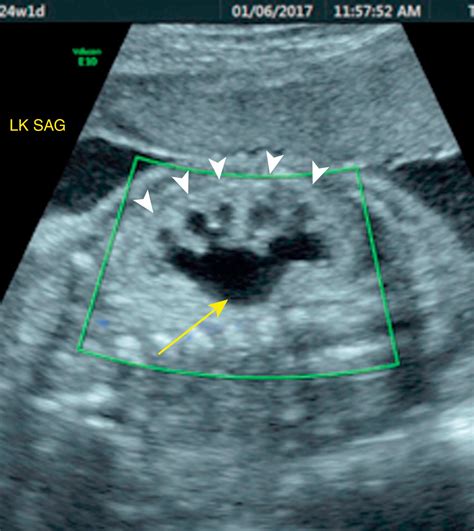

Pyelectasis of the fetus is typically diagnosed during routine prenatal ultrasound examinations. The diagnosis is based on the measurement of the anteroposterior diameter (APD) of the renal pelvis. The severity of pyelectasis is categorized as follows:

Severity APD Measurement (mm)

Mild 4-7

Moderate 7-10

Severe Greater than 10